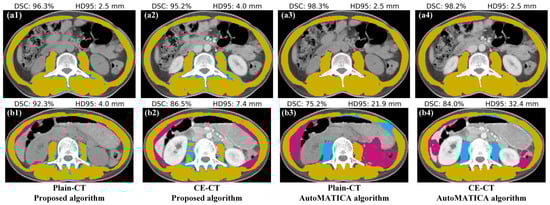

3.1. Segmentation Accuracy Comparison with AutoMATICA

| Metrics † | Algorithm | Image Series | Summary | p-Value * | |

|---|---|---|---|---|---|

| Plain-CT | CE-CT | ||||

| DSC (%) | Proposed | 93.2 ± 1.6 | 93.2 ± 2.2 | 93.2 ± 1.9 | <0.01 |

| AutoMATICA | 94.0 ± 4.6 | 94.2 ± 3.4 | 94.1 ± 4.1 | ||

| precision (%) | Proposed | 97.0 ± 2.2 | 96.5 ± 3.5 | 96.7 ± 2.9 | <<0.01 |

| AutoMATICA | 92.5 ± 6.1 | 93.0 ± 4.8 | 92.7 ± 5.5 | ||

| recall (%) | Proposed | 89.7 ± 3.0 | 90.2 ± 2.9 | 90.0 ± 2.9 | <<0.01 |

| AutoMATICA | 95.7 ± 4.0 | 95.7 ± 4.0 | 95.7 ± 4.0 | ||

| HD95 (mm) | Proposed | 4.6 ± 1.1 | 4.9 ± 1.5 | 4.8 ± 1.3 | <0.01 |

| AutoMATICA | 6.9 ± 4.8 | 7.8 ± 6.5 | 7.4 ± 5.7 | ||

| ASD (mm) | Proposed | 0.8 ± 0.2 | 0.8 ± 0.3 | 0.8 ± 0.2 | >0.05 |

| AutoMATICA | 0.9 ± 0.6 | 0.9 ± 0.6 | 0.9 ± 0.6 | ||